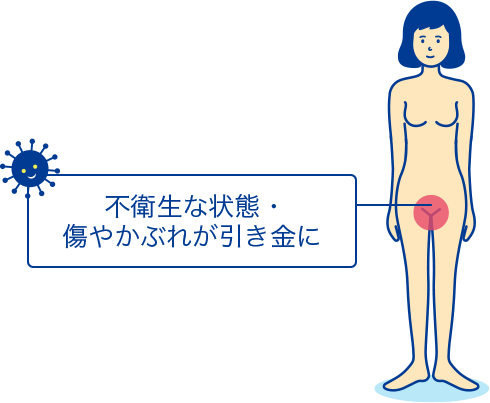

外陰炎の解説 症状や原因 治療について Std研究所

デリケートゾーン 陰部 のかゆみの症状 原因 くすりと健康の情報局